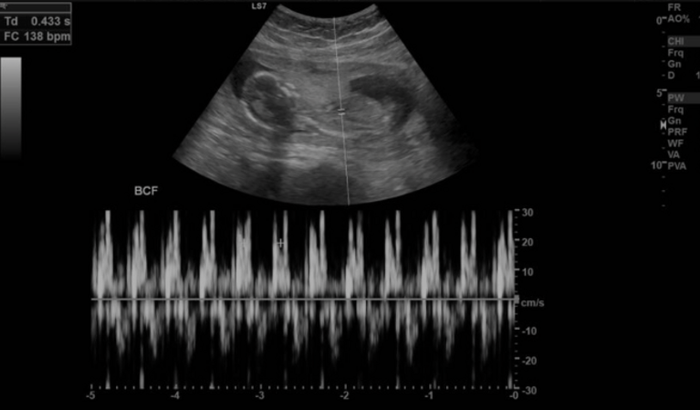

Eu me chamo Thayana. Estou precisando do valor de R$3800,00 para o parto do nosso bebê. Tenho a doença de Von willebrand ( um problema de sangue genético), meu parto é de risco. Hoje estou com 8 meses, e com esse valor minha médica de pré Natal consegue um parto com sua equipe e de forma segura, tanto pra mim quanto para o meu bebê. Quem puder ajudar serei eternamente grata por isso. O parto está previsto pra novembro. Que Deus abençoe ainda mais todos você .